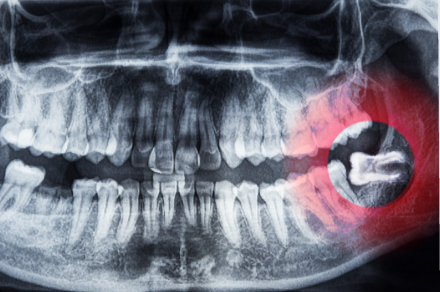

親知らずについて

親知らずの知識

親知らずは全て抜いたほうが良いのか?